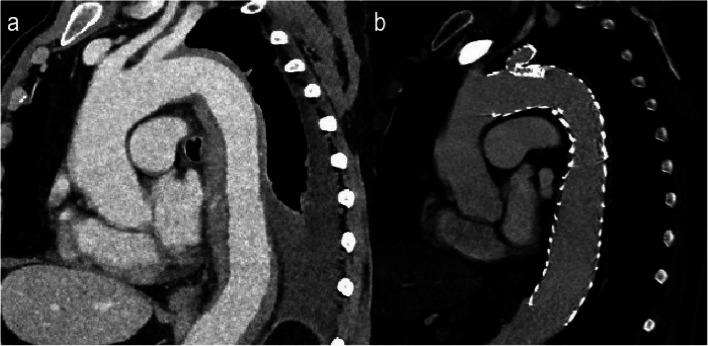

Background: Thoracic endovascular aortic repair (TEVAR) has been a feasible treatment option since the first stent graft was approved by the FDA in 2005, and is now the recommended method for treating most descending aorta pathology in the current clinical practice guidelines. Indications for TEVAR include descending aorta aneurysms, traumatic aortic injury and pathology that presents as acute aortic syndrome. More often than not the lesion that needs to be excluded is quite close or contains the distal aortic arch, thus requiring the coverage of the left subclavian artery (LSA) origin, a practice that has been associated with severe complications. Contraindications to LSA coverage resulted in the development of various surgical and endovascular LSA revascularization techniques.

Materials and methods: Branched stent grafts containing a single branch for the LSA are a rapidly evolving technology regarding LSA reconstruction during TEVAR. The aim of this article is to demonstrate our center's experience using a novel off-the-shelf single-branched stent graft, the GORE® TAG® Thoracic Branch Endoprosthesis (TBE) (W. L. Gore & Associates, Inc, Flagstaff, Ariz, USA). The GORE® TAG® TBE is commercially available in Europe since early 2024. We have so far, since February 2024, treated 12 patients using this endograft, successfully treating all types of aortic lesions.